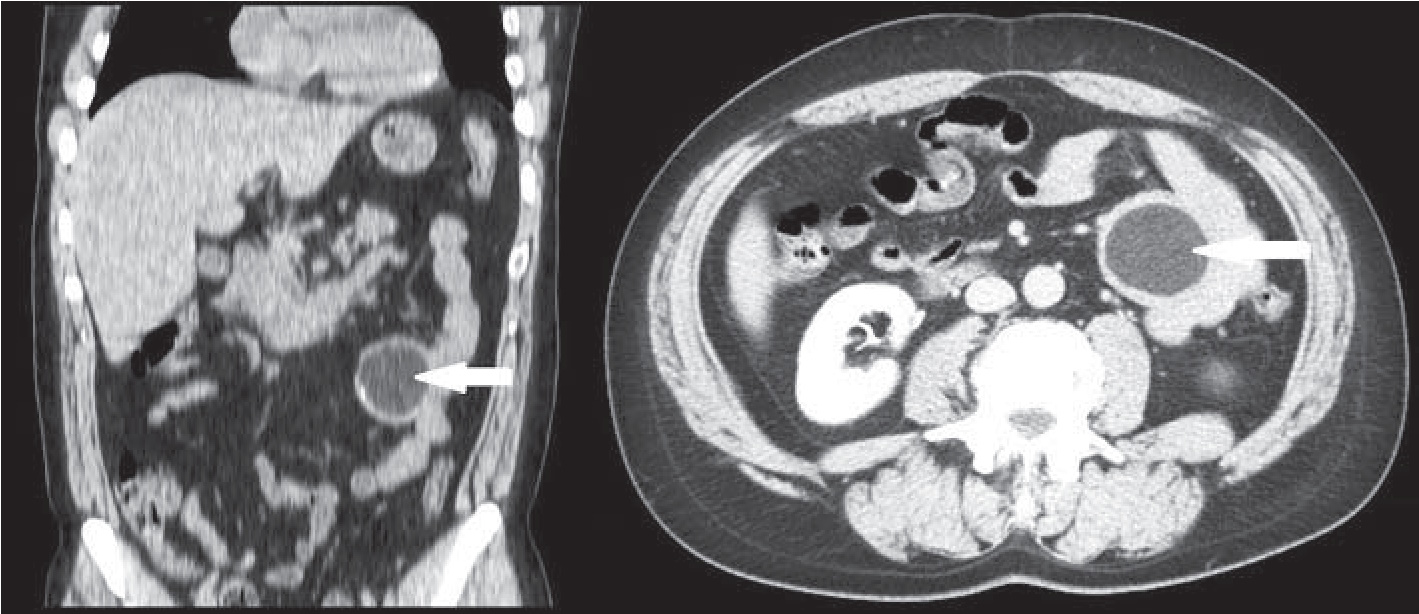

Результаты и их обсуждение. Пациент обследован амбулаторно. По данным УЗИ органов брюшной полости, слева в мезогастрии на уровне пупка между петлями кишечника лоцируется аваскулярное гипоэхогенное округлое образование с четким ровным контуром, с гиперэхогенной капсулой, размерами 65×67×70 мм. По данным мультиспиральной компьютерной томографии (МСКТ) органов брюшной полости, в проекции левого фланка на уровне L2−L3 в межпетельном пространстве определяется округлое кистоподобное образование жировой плотности с четкими ровными контурами, интимно прилежащее к стенке тонкой кишки, с толстой капсулой толщиной от 4 до 7 мм, общими размерами 66×64×68 мм, по внутреннему контуру капсулы выявляются единичные плоские кальцинированные включения (рис. 1). При введении контрастного препарата накопления не выявляется. Пациент проконсультирован онкологом, убедительных данных за онкологический характер изменений не получено.

Рис. 1. МСКТ-снимки кисты брыжейки тонкой кишки